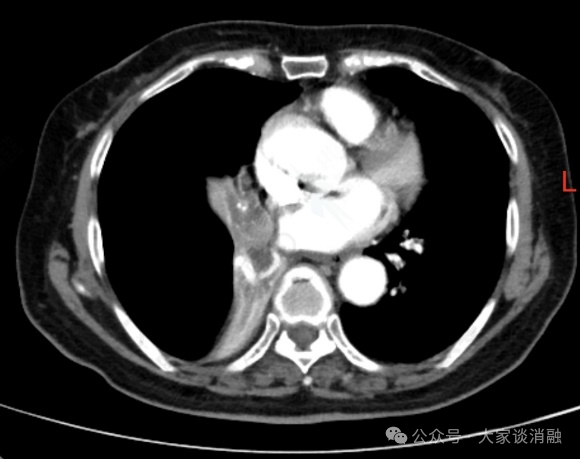

夏奶奶近两年来一直被间断的胸闷、气短、咳嗽、咳痰困扰。半月前,她的病情急剧加重,出现了痰中带血的症状,家人紧急送至东院区。呼吸与危重症医学科阎杰副主任医师接诊后,立即为夏奶奶进行胸部增强CT检查。结果提示“右肺门增大,右肺主支气管内结节状软组织密度灶,右肺下叶不张”,高度怀疑恶性肿瘤。

*患者CT检查

在与家属全面沟通并取得同意后,11月17日,尚东主任在王丽主管护师、李雪护师的密切配合下,成功为夏奶奶实施了PTS化学消融术。术中,尚东主任通过支气管镜将药物甲苯磺酰胺注射液(PTS)精准注射到肿瘤内部,术中即可见肿瘤组织迅速回缩、结构变得疏松,气管镜得以成功探入此前被堵塞的右中间支气管,手术过程顺利。术后3天,复查气管镜,原本狭窄的管腔已显著好转,右肺下叶及右中叶支气管开口清晰可见,夏奶奶的呼吸变得顺畅,气短症状极大缓解,未再出现咯血,目前已顺利出院。